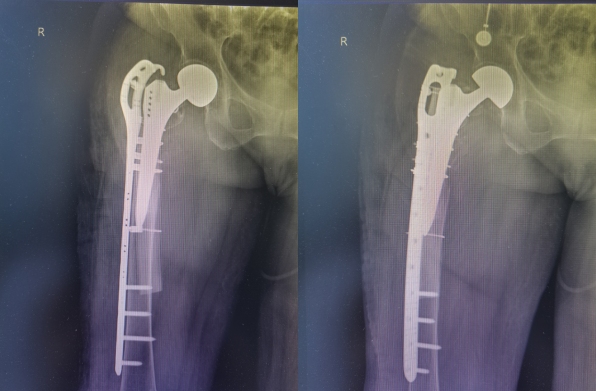

术前X线片